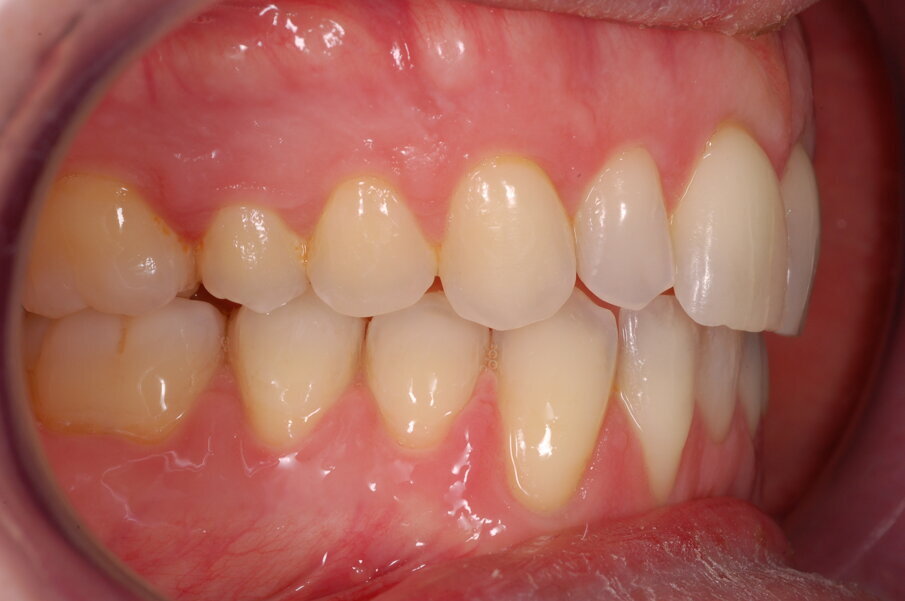

Diagnosi ed eziologia Un uomo sano di 39 anni si è presentato nel nostro studio ortodontico lamentando un aspetto dentale poco attraente e la paura della chirurgia ortognatica proposta da un altro ortodontista. Clinicamente, il profilo del paziente era rettilineo e la vista frontale non mostrava alcuna asimmetria facciale. L’esame funzionale non ha rivelato alcuna deviazione mandibolare o riduzione dei movimenti. Il paziente non aveva dolori articolari e non sono stati rilevati rumori articolari. Era presente una lieve occlusione molare bilaterale di Classe II, un morso aperto e un grave affollamento in entrambe le arcate. L’affollamento era particolarmente grave nell’arcata mandibolare, sebbene mancasse l’incisivo centrale mandibolare destro. Gli incisivi mascellari erano di piccole dimensioni, suggerendo una discrepanza dell’indice di Bolton se fossero stati presenti tutti e quattro gli incisivi mandibolari. Erano inoltre presenti un morso incrociato nella regione dell’incisivo laterale superiore sinistro e una grave rotazione distale del secondo premolare mandibolare sinistro (Figg. 1-8).

Figg. 1-8_Fotografie facciali e intraorali pre-trattamento.